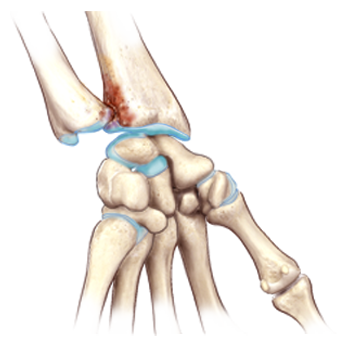

Bones and trauma

Camp 4

1.0 ECMECs

Look into several conditions, including fractures, cysts, and lesions